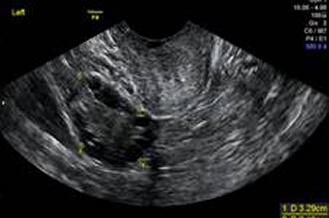

卵巢巧克力囊腫

子宮肌瘤、卵巢巧克力囊腫、子宮內膜厚度、卵巢基礎濾泡數量…等,都可能影響受孕,這些資訊可以藉由陰道超音波檢查而得知。

超音波探頭伸入陰道後,可以縮短探頭與子宮和卵巢的距離,看到子宮和卵巢更多的細節。檢查約2~3分鐘內可完成。